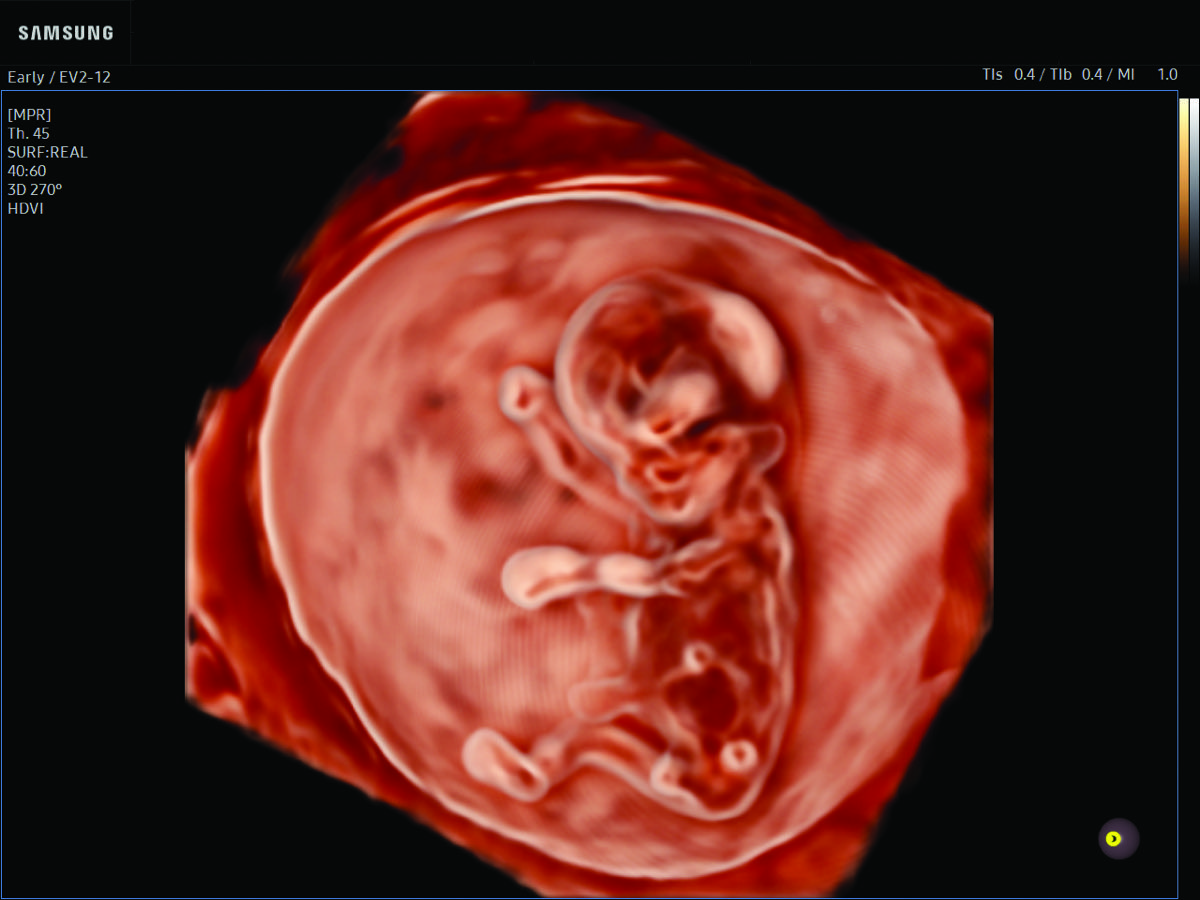

Comprehensive, advanced and expert MFM care for high-risk pregnancies

- Fetal anomalies